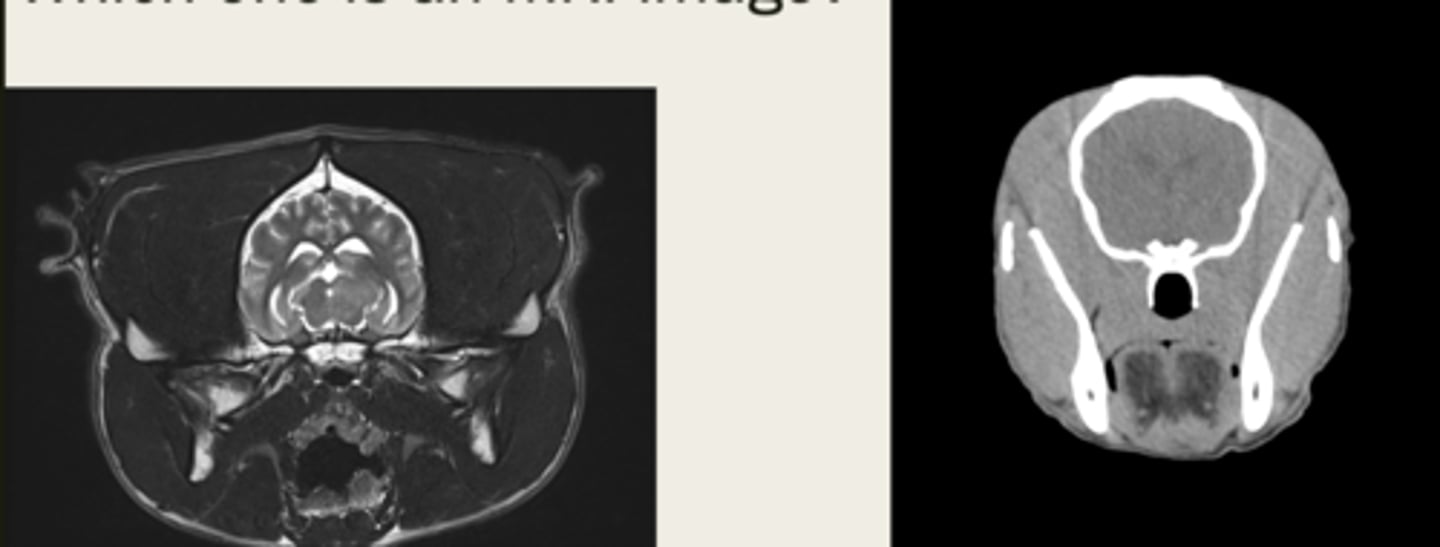

CT

is the left image a CT or MRI?

left- CT

right- MRI

which images are CT and which are MRI?

-cross sectional

-same area

-TRANSVERSE PLANE

how are these images the same?

right- bright bone

left- less bright bone, more definition in tissue

how are these images different?

left- MRI

right- CT

which one is the CT and which is the MRI?